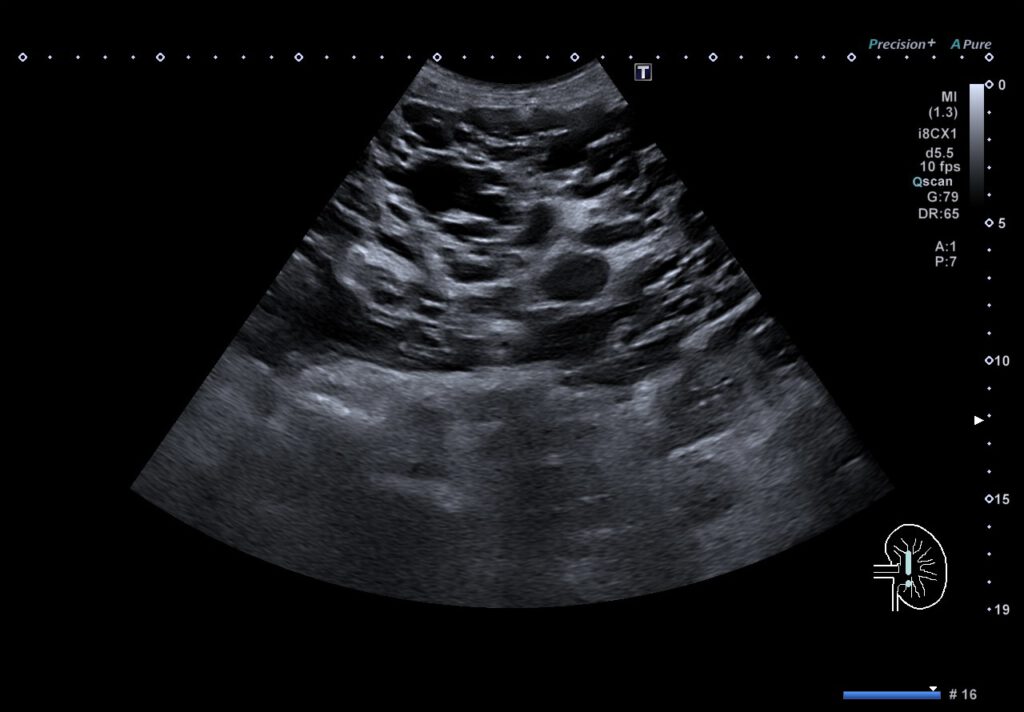

59-jährige Patientin mit infizierter Leberzyste bei polyzystischer Leber- und Nierendegeneration.

Oberbauchschmerzen, Schüttelfrost und Fieber führten zur stationären Aufnahme. In der Abdomensonographie wurden multiple Zysten der Leber und Nieren nachweisbar, wobei im rechten Leberlappen eine vermehrt echoreich gefüllte liquide Formation auffiel. Nach Probepunktion entleerte sich Eiter, weswegen eine perkutane Drainage angelegt wurde. Mikrobiologisch gelang der Nachweis eines E. coli. Bei deutlich fallenden Infektparametern und symptomfreier Patientin wurde die Drainage 7 Tage nach Anlage entfernt.